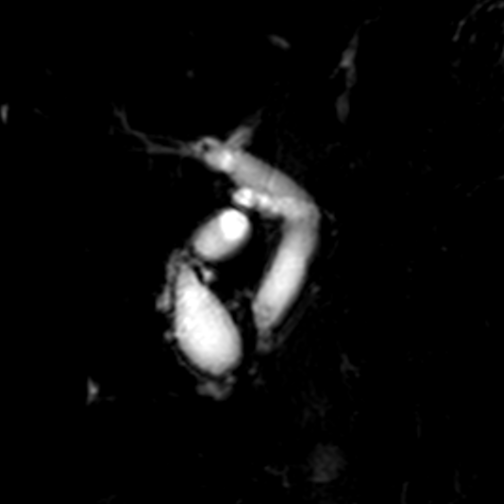

▲患者MRCP(胰胆管水成像)

每个并发症对于患者来说都是难以承受的打击。但此次腹痛,若不积极手术,胆总管结石进一步发展为化脓性胆管炎,病情则有可能会危及生命!

在完善术前准备及与麻醉科、肺病科相关科室会诊讨论后,外一科顾卯林主任团队为患者行腹腔镜下胆囊切除+胆总管切开取石+胆总管一期缝合术。